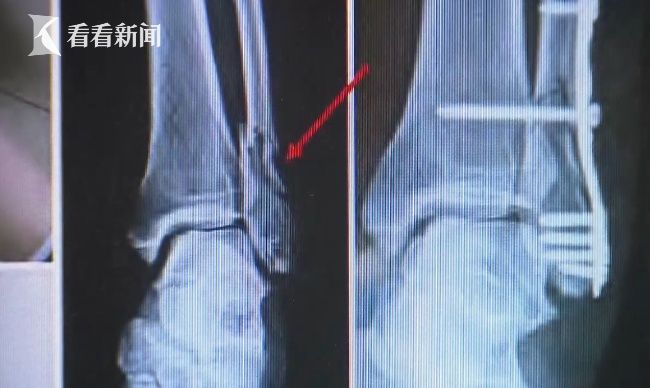

浦东检察院检察官助理吴琰琰介绍,因为她不满前妻在微信上和别人有频繁联系。所以持家里的铁棍,对前妻实施殴打当时就直接打的昏迷,经过伤势鉴定构成了轻伤一级骨折行为,伤势是非常严重的。

犯罪嫌疑人张某说,当时我是想打她两下教训教训她,她不老实吗,手乱动脚乱动就打到她腿上去了,当时也没有想会那么严重,结果腿骨折了。